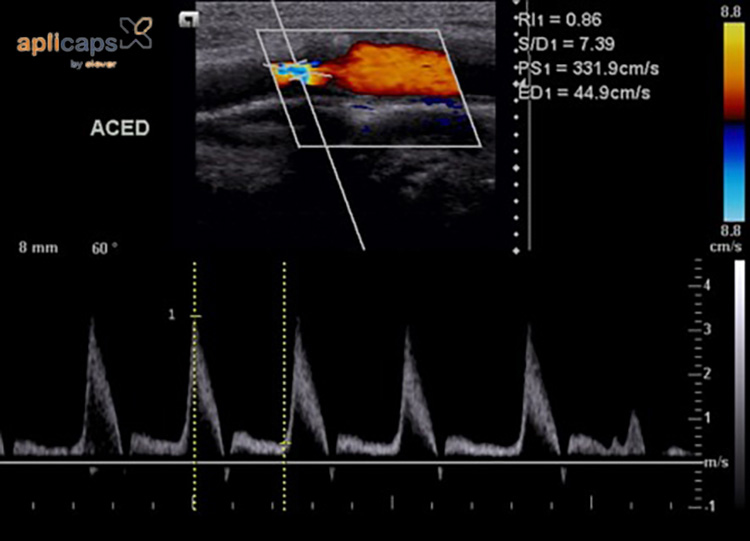

Chỉ số PI (pulsatility index) trong siêu âm thai Doppler là chỉ số phản ánh nhịp đập của động mạch. Kỹ thuật này được sử dụng để đánh giá lưu lượng máu và tốc độ truyền máu tại các vị trí như động mạch não giữa, tim, rốn và động mạch tử cung. Thông qua những chỉ số này, bác sĩ có thể xác định mức độ cung cấp oxy và dinh dưỡng từ mẹ đến thai nhi, từ đó chẩn đoán tình trạng phát triển của thai nhi trong tử cung.

Chỉ số PI cho biết nhịp đập của động mạch thai nhi